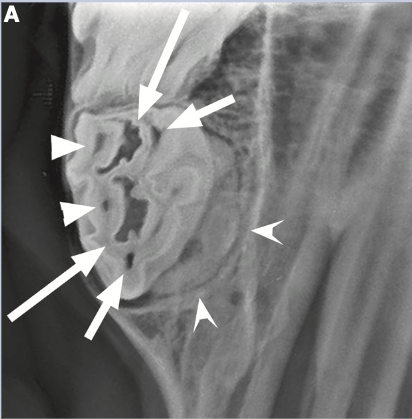

The concave arrows represent what imaging finding/diagnosis?

JVD 2011, Issue 3 “Essential Considerations for Equine Oral Exam, Diagnosis and Treatmemt” Menzies, Lewis, Reiter, Lundstrom

A

Hypercementosis